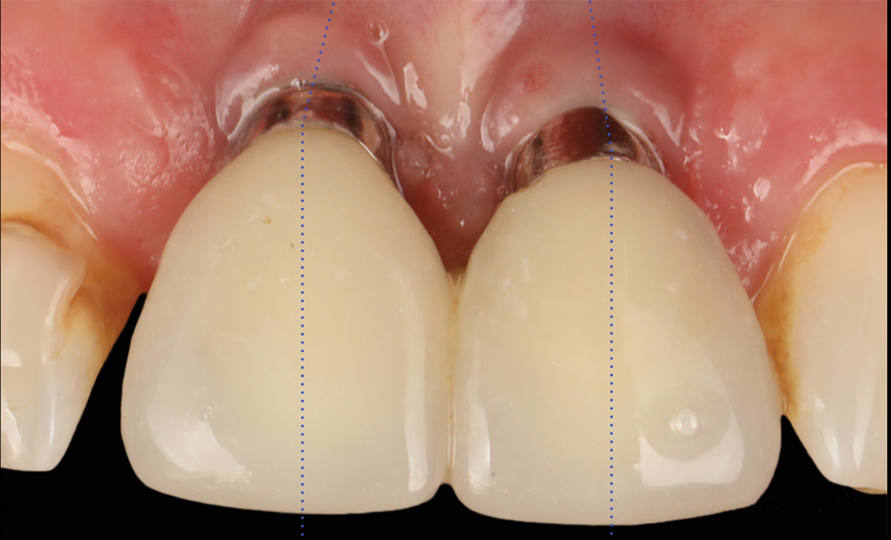

The flap was closed using simple interrupted sutures (7-0 PGA, butterfly), with the mid-portion of the flap folded and rolled to increase the thickness and height of the interproximal soft tissue between the two implants (Figure 12). 3D-printed temporary crowns were adapted to the flap and delivered (Figure 13). Further modifications of the temporary crowns were performed between 1 month and 3 months, when the final ceramic restorations were delivered.

Fig 13. Temporary crowns.

Figure 13

Fig 15. Clinical comparison of the volumetric gain obtained with the intervention, frontal views. Fig 15: Frontal view at baseline. Fig 16: Frontal view at 1-year post-treatment.

Figure 15